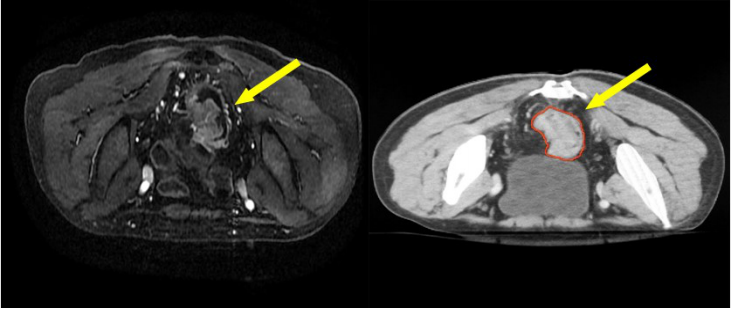

a) GTV(紅色)通過對比定位 MR 圖像,在 CT 定位圖像完成 GTV 的勾畫(圖 1)。

圖 1 直腸癌 GTV 勾畫示例